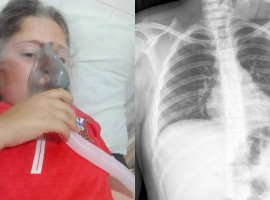

Se trata de Ninfa Chávez de 40 años de edad, que a parte de su nula visión, cuenta con varias enfermedades y reside en una precaria vivienda junto con su padre Fernando Chávez, quien se dedica al reciclaje.

“Ninfa necesita intervención médica de manera urgente, yo algunas veces la traigo a casa para ducharla, alimentarla, se queda sola por varias horas en su casa mientras su papá sale a trabajar, pero yo me preocupo mas por la salud de ella, además ni cama tienen”, indicó una de las vecinas.